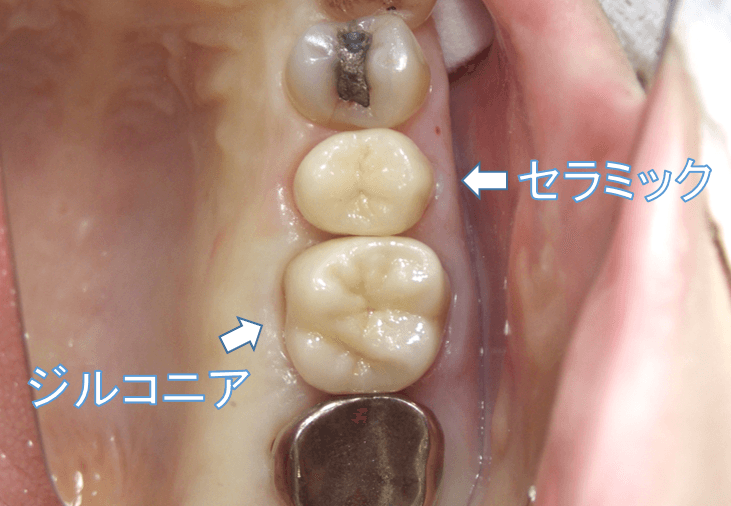

審美歯科治療 セラミック ジルコニア

こんにちは。 南館歯科クリニックの院長の木村です。 左上の審美治療のケースをご紹介します。 今回は3歯治療を行っていますが、それぞれ2次虫歯での再治療です。 根管治療が必要…